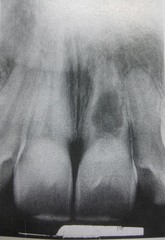

Scalloping around the root (radiographic terms used to describe lesions in bone)

A radiolucent lesion that extends between the roots, as seen in a traumatic bone cyst; this lesion appears to extend up the periodontal ligament.